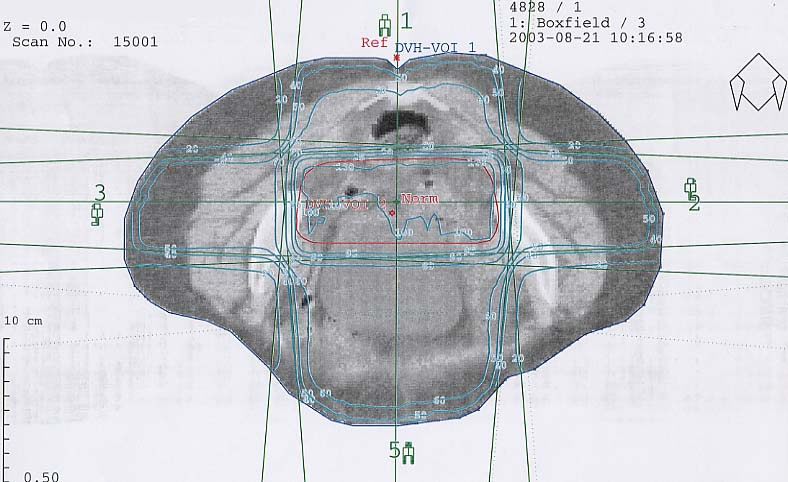

Gynäkologische Tumore des Beckens: Bestrahlungsplan

Bestrahlungspläne